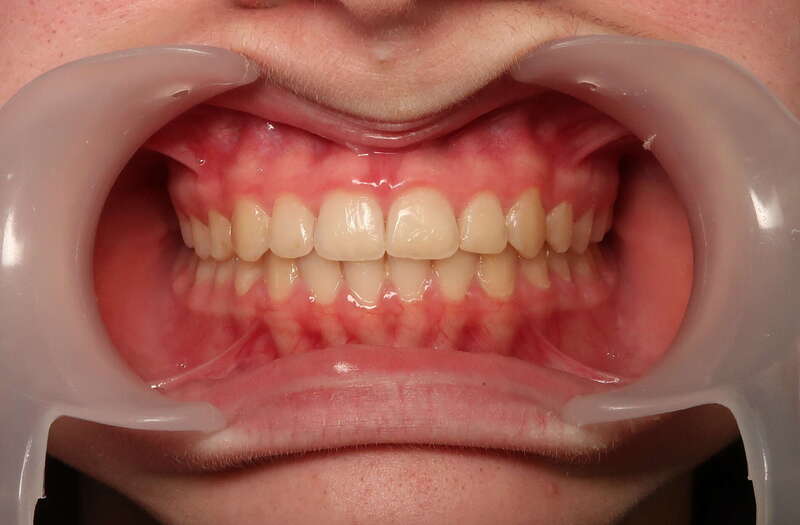

Cas n°1 traité par aligneurs - adolescent

Ce cas d’une adolescente illustre la correction d'une Classe II avec supraclusion par aligneurs. La stratégie thérapeutique a reposé sur une distalisation séquentielle de l'arcade supérieure. Ce mouvement précis a permis de reculer les dents maxillaires étape par étape pour annuler le surplomb (overjet) sans extractions.

Résultats clés :

• Correction fonctionnelle : Retour à un engrènement de Classe I stable et correction du recouvrement vertical.

• Esthétique restaurée : Harmonisation globale du sourire et du profil.

• Approche moderne : Un traitement discret, confortable et hautement prévisible.

Le résultat final montre une occlusion saine et un sourire parfaitement aligné, garantissant une santé dentaire et articulaire optimale pour l'avenir.